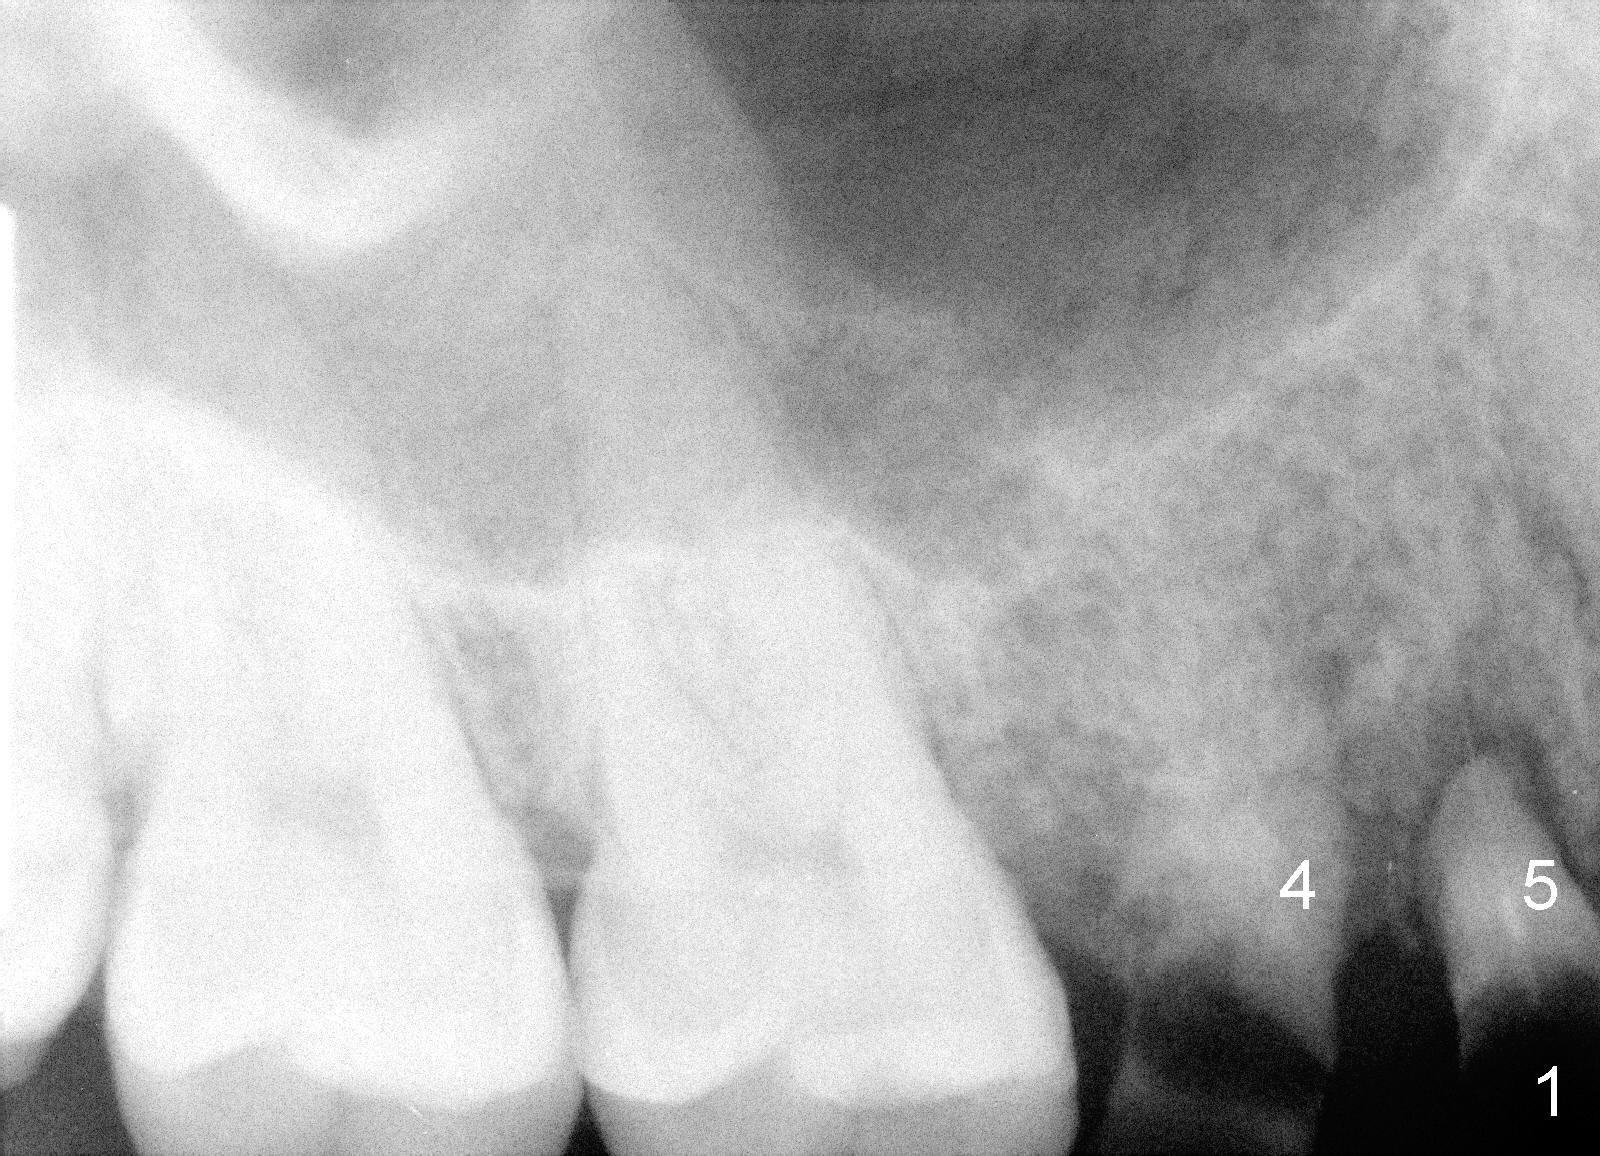

2. Take PA (Fig.1), Photos

3. PA device, for lower posterior, use endo device; for upper, regular; for upper premolar, anterior if root and bone are long.  Today the patient’s mouth is small.  No.1 sensor was used with anterior PA device later (Fig.4-6)